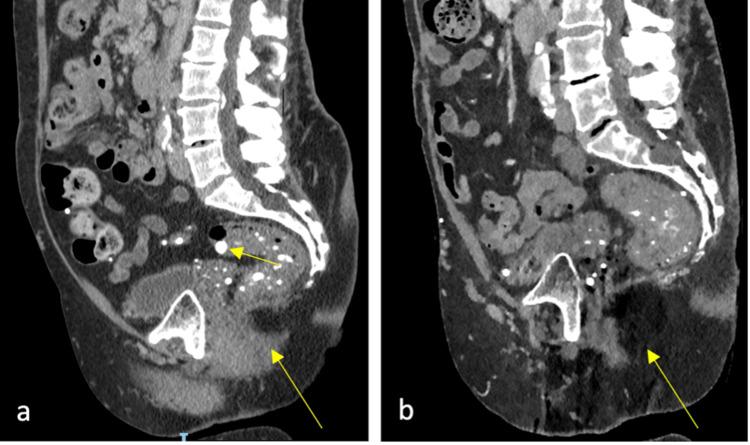

马富西综合征是一种极其罕见的先天性疾病,其特征是主要在四肢出现多发性内生软骨瘤和血管瘤,并伴有各种肿瘤。马富西综合征患者的结肠和盆底功能从未被研究过。我们报告一例病例,该病例说明了一名女性患者因马富西综合征的血管畸形继发结肠和盆底功能障碍的管理挑战。